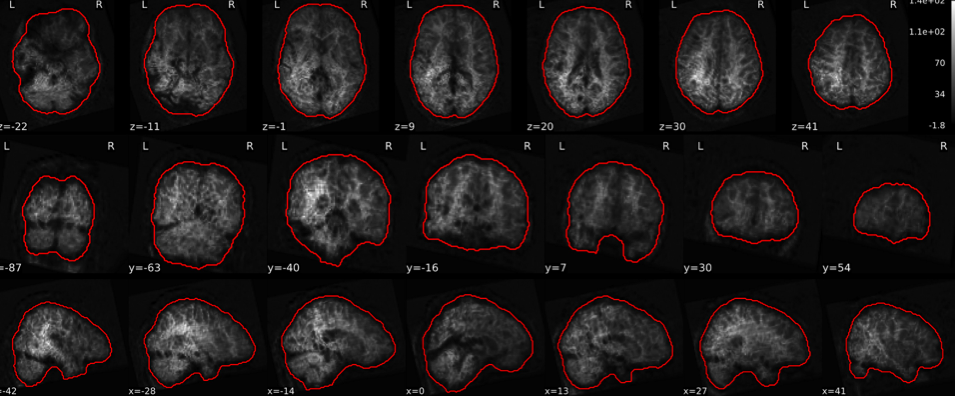

EPI tSNR

In the signal to noise ratio images of the resting state image the desired signal is compared to the amount of background noise. It is important to check all the views (sagittal, coronal, axial) because some artefacts (e.g., stripes) may be evident only in one particular view.

Example of a good subject

- Signal to noise is symmetrically distributed and there is no signal distortion

Example of a bad subject

- Asymmetry

- Potential signal distortion (might represent an artefact)

- Signal drop-out

- Stripes artefact

Clear large artefact (e.g., zebra stripes in example 1) are worth the exclusion of the subject. If you are unsure, check the other quality metrics for that subject to decide whether they should be excluded.

Summary

| good | bad |

|---|---|

| Symmetrical distribution of noise and signal | Asymmetry |

| No disruptions of the signal (no “black patches”) |

Potential signal disruptions (could be related to artefacts) |

| No stripes (sign of high motion) |

Signal drop |

| Stripe artefacts (“zebra” stripes due to motion) |